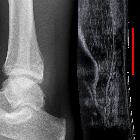

Plain radiograph

Plain radiographs may show soft tissue swelling and obliteration of pre-Achilles fat pad (Kager's triangle).

Ultrasound

For partial thickness tears

- there is often enlargement of the tendon ( >1 cm) with abnormally hypoechoic or anechoic areas within which correspond to the tear and associated adjacent tendinosis

For full thickness tears

- often shows separation of the torn ends with a contour change of the tendon

- there is acoustic shadowing at the margins of the tear from sound beam refraction, and adjacent hypoechoic tendinosis